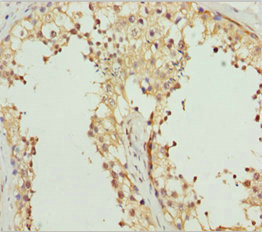

Immunohistochemistry of paraffin-embedded human?testis tissue using CSB-PA862045DSR1HU at dilution of 1:100